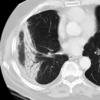

Radiation case 1

Date: 07/07/2004

Views: 4264